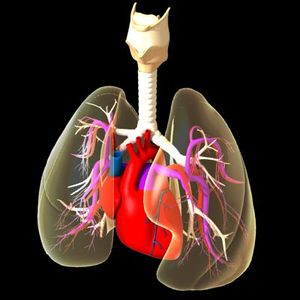

يحتوي الدم الذي يدخل الجانب الأيمن من القلب على ثاني أكسيد الكربون، وهو غاز فاسد تفرزه الخلايا والأنسجة في عملية إنتاج الطاقة. ويدخل الدم الأذين الأيمن عن طريق الوريد الأجوف العلوي والوريد الأجوف السفلي. وعندما يمتلئ الأذين ينقبض، ضاخًا الدم في البطين. وحينما يمتلئ البطين فإن الضغط المتولد يجعل الصمام المثلث الشرف ينغلق، والصمام الرئوي المؤدي للشريان الرئوي ينفتح، وبعدها ينقبض البطين ويدفع الدم في الشريان الرئوي ثم إلى الرئتين. وفي الرئتين يستبدل الأكسجين بثاني أكسيد الكربون. ثم ينساب الدم المؤكسد في الأوردة الرئوية للجزء الشمالي من القلب. انظر: الرئة.

ضخ الدم لكل أجزاء الجسم

يدخل الدم المؤكسد من الرئتين ويملأ الأذين الأيسر، ومن ثم ينقبض الأذين ليضخ الدم عبر الصمام التاجي في البطين الأيسر. وبعد أن يمتلئ البطين بالدم ينغلق الصمام التاجي وينفتح صمام الأبهر. ويتدفق الدم في الأبهر ويتوزع عن طريق الشرايين إلى خلايا وأنسجة الجسم المختلفة.